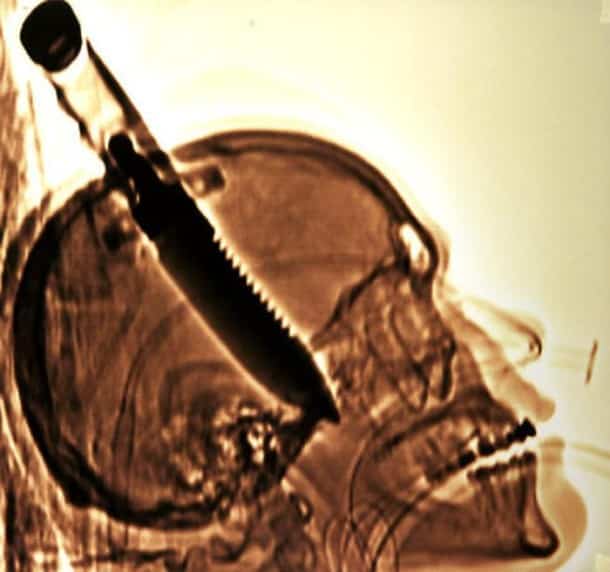

Accident, incident de pistolet à clous ou introductions douteuses de choses douteuses dans des parties douteuses de leur corps…voilà un petit aperçu de ce que voient les médecins au quotidien…

Certaines radiographies sont impressionnantes mais relèvent d’accidents…d’autres en revanche…